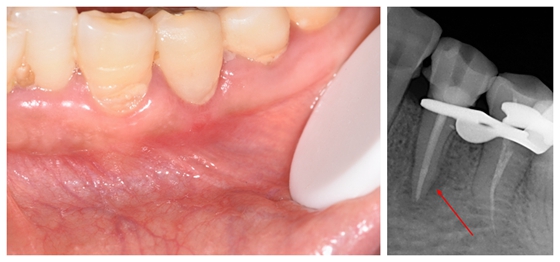

半年前,喻女士无意中发现左边下牙龈冒出了个小脓包,两天过后,她发现脓包并未有消退的迹象,便到湘雅常德医院口腔科就诊。据病人回忆,早在牙龈冒出脓包前,她就感到左下方的牙齿经受冷水会有刺痛感,甚至严重影响到睡眠。通过进一步详细询问病史、口腔检查及拍摄小牙片,医生明确了喻女士牙龈上的脓包来源:牙面上深达髓腔的深楔状缺损引发牙齿慢性根尖周炎,引起牙龈冒出脓包。要想消除脓包,就要对这颗牙进行根管治疗,消除炎症。

就诊第一天,患者根尖周低密度影

接下来,口腔科医生对喻女士的这颗牙进行了根管治疗的第一步:根管清理成形 ,补上了牙面上的深楔状缺损。一周后的复诊,喻女士牙龈上的脓包已经完全消失了!口腔科医生随后完善了这颗牙的根管充填及严密的冠方封闭。今日,再次到访的喻女士高兴地对医生说:“这半年来,我这颗牙终于安静了,再也没出现疼痛,也没有长脓包了,牙齿上的填充物也还好好的,没有掉。”

治疗一周后,根管填充牙位